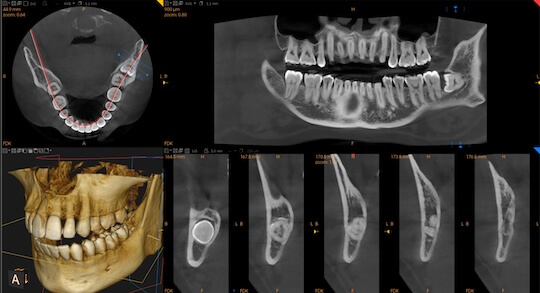

數碼化精確診斷,大幅降低手術風險

精確定位智齒與主要神經線的距離,大幅提升複雜手術的安全性。

採用 CBCT 進行3D掃描,獲取智慧齒與神經、牙根的距離。

採用 CBCT 掃描,清晰掌握與神經線及牙根距離,提升治療安全性。

透過 3D CBCT 掃描,醫生能精確掌握神經位置。對於風險極高的個案,醫生會提供專業建議或分階段處理。